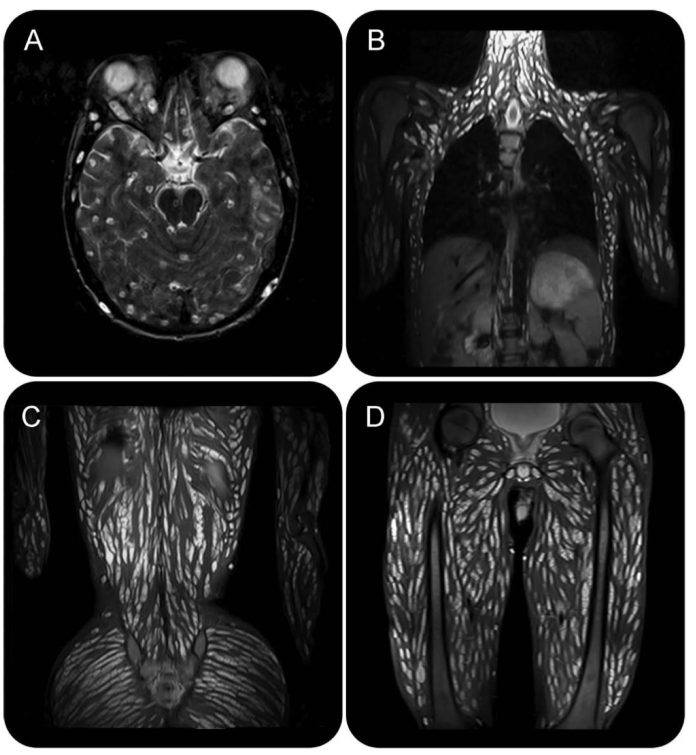

แพทย์ตรวจร่างกายพบความผิดปกติของกล้ามเนื้อทั่วร่างกาย มีลักษณะพอง แข็ง แน่นผิดธรรมชาติ ไม่ใช่แบบกล้ามเนื้อนักกีฬา จึงตัดสินใจส่งตรวจ MRI สมอง ผลตรวจสร้างความตกใจอย่างมาก เมื่อพบจุดกลมจำนวนมากในเนื้อสมอง มีทั้งลักษณะใสและขุ่น ขนาดแตกต่างกัน

และเมื่อไล่ตรวจภาพลงมาทั่วร่างกาย พบถุงลักษณะเดียวกันกระจายอยู่แทบทุกส่วน ไม่ว่าจะเป็นหนังศีรษะ กล้ามเนื้อตา คอ ผนังอก หน้าท้อง กล้ามเนื้อข้างกระดูกสันหลัง ก้น เชิงกราน แขน และขา แทบไม่มีกล้ามเนื้อมัดใดรอดพ้น จนแพทย์เปรียบเปรยว่าร่างกายของผู้ป่วยกลายเป็น “อาณาจักรของพยาธิ”

แพทย์วินิจฉัยว่าเป็นภาวะ การติดเชื้อพยาธิตืดหมูแบบกระจาย (disseminated neurocysticercosis) ซึ่งไม่ได้จำกัดอยู่แค่ในสมอง แต่ฝังตัวอยู่ทั่วร่างกาย โดยอาการรุนแรงที่เกิดขึ้นไม่ได้มาจากการอักเสบจากการตายของพยาธิ แต่เกิดจากแรงกดของถุงจำนวนมหาศาลที่เบียดสมอง ส่งผลให้เกิดภาวะความดันในกะโหลกศีรษะสูง ทำให้ปวดศีรษะ อาเจียน ชัก และซึมลง